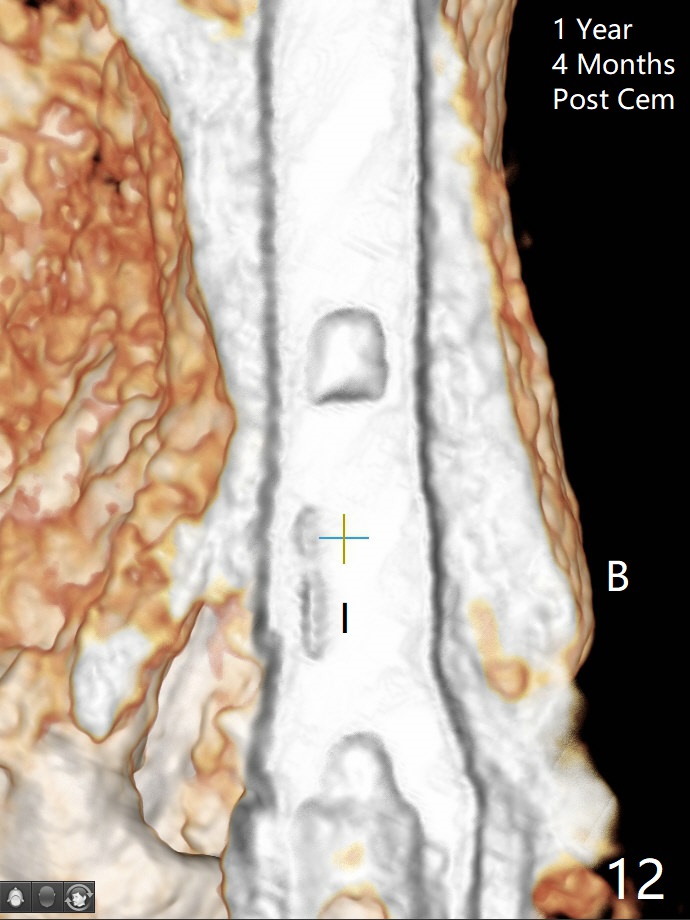

In spite of severe apical infection (Fig1,2 *), a thin narrow strip of the buccal plate (arrowheads, corresponding to the keratinized gingiva) is present when the tooth #11 is extracted. The thin bone keeps the bulging alveolus, i.e., reservoir for bone graft (Vanilla/Osteogen Fig.4 *) after placement of a 3.8x16 mm implant (Fig.3,4). A 4.5x1 mm temporary abutment, placed and trimmed for an immediate provisional, seems to be short in cuff. When an implant is placed deep to prevent periimplantitis, the cuff should be longer, i.e., 3 mm. X-ray should be taken for the depth confirmation after temporary abutment placement. Eight days postop, the mesial gingiva erythema has subsided (Fig.5 < (P: provisional)), while the apical swelling is no longer tender and most likely due to packed bone graft (*). Panoramic X-ray taken 2 weeks postop shows the clearance from the nasal cavity or the maxillary sinus (Fig.6). While the hard tissue around the implant seems to be healthy 5 months postop (Fig.7), the soft tissue is not (Fig.8). The temporary abutment is changed to a cemented one (4.5x5(2) mm) for impression (Fig.8). Since the neighboring crowns are PFM (Fig.6), the new crown will be made of the same material for shade match. Indeed PFM helps shade match in this case as well (Fig.9,10). Switching abutments (from temporary to cemented) makes it difficult to seat the crown. Post cementation X-ray leaves record for future contact loosening. The buccal gingiva remains erythematous associated with open margin (Fig.11 >) 1 year 4 months post cementation. There is no obvious bone loss 1 year 4 months post cementation (Fig.12). It appears that the crown and abutment need to be changed. Although the gingival margin remains erythematous, the gingival hemorrhage is basically lacking due to better oral hygiene during Shelter at Home (1 year 9 months post cementation, Fig.13). Change in abutment and crown will be conducted post coronavirus pandemic. In fact the abutment is incompletely seated (Fig.14 <). In addition, the tooth #12 is symptomatic with PARL associated with the buccal root (*). CBCT indicates possible buccal root fracture (Fig.15,16 ^) and loss of the buccal plate (Fig.16 <).